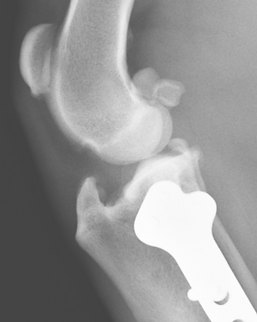

Pins and wires are used to stabilize a tibial tuberosity transposition, the most common surgery for patellar luxation.

Complex stifle trauma repair.